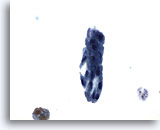

Urine obtenue par cathétérisme, résultat négatif

Les groupes de cellules sont souvent détruits par le cathétérisme.

20x

Urine obtenue par cathétérisme, résultat négatif

Les groupes de cellules sont souvent détruits par le cathétérisme.

20x